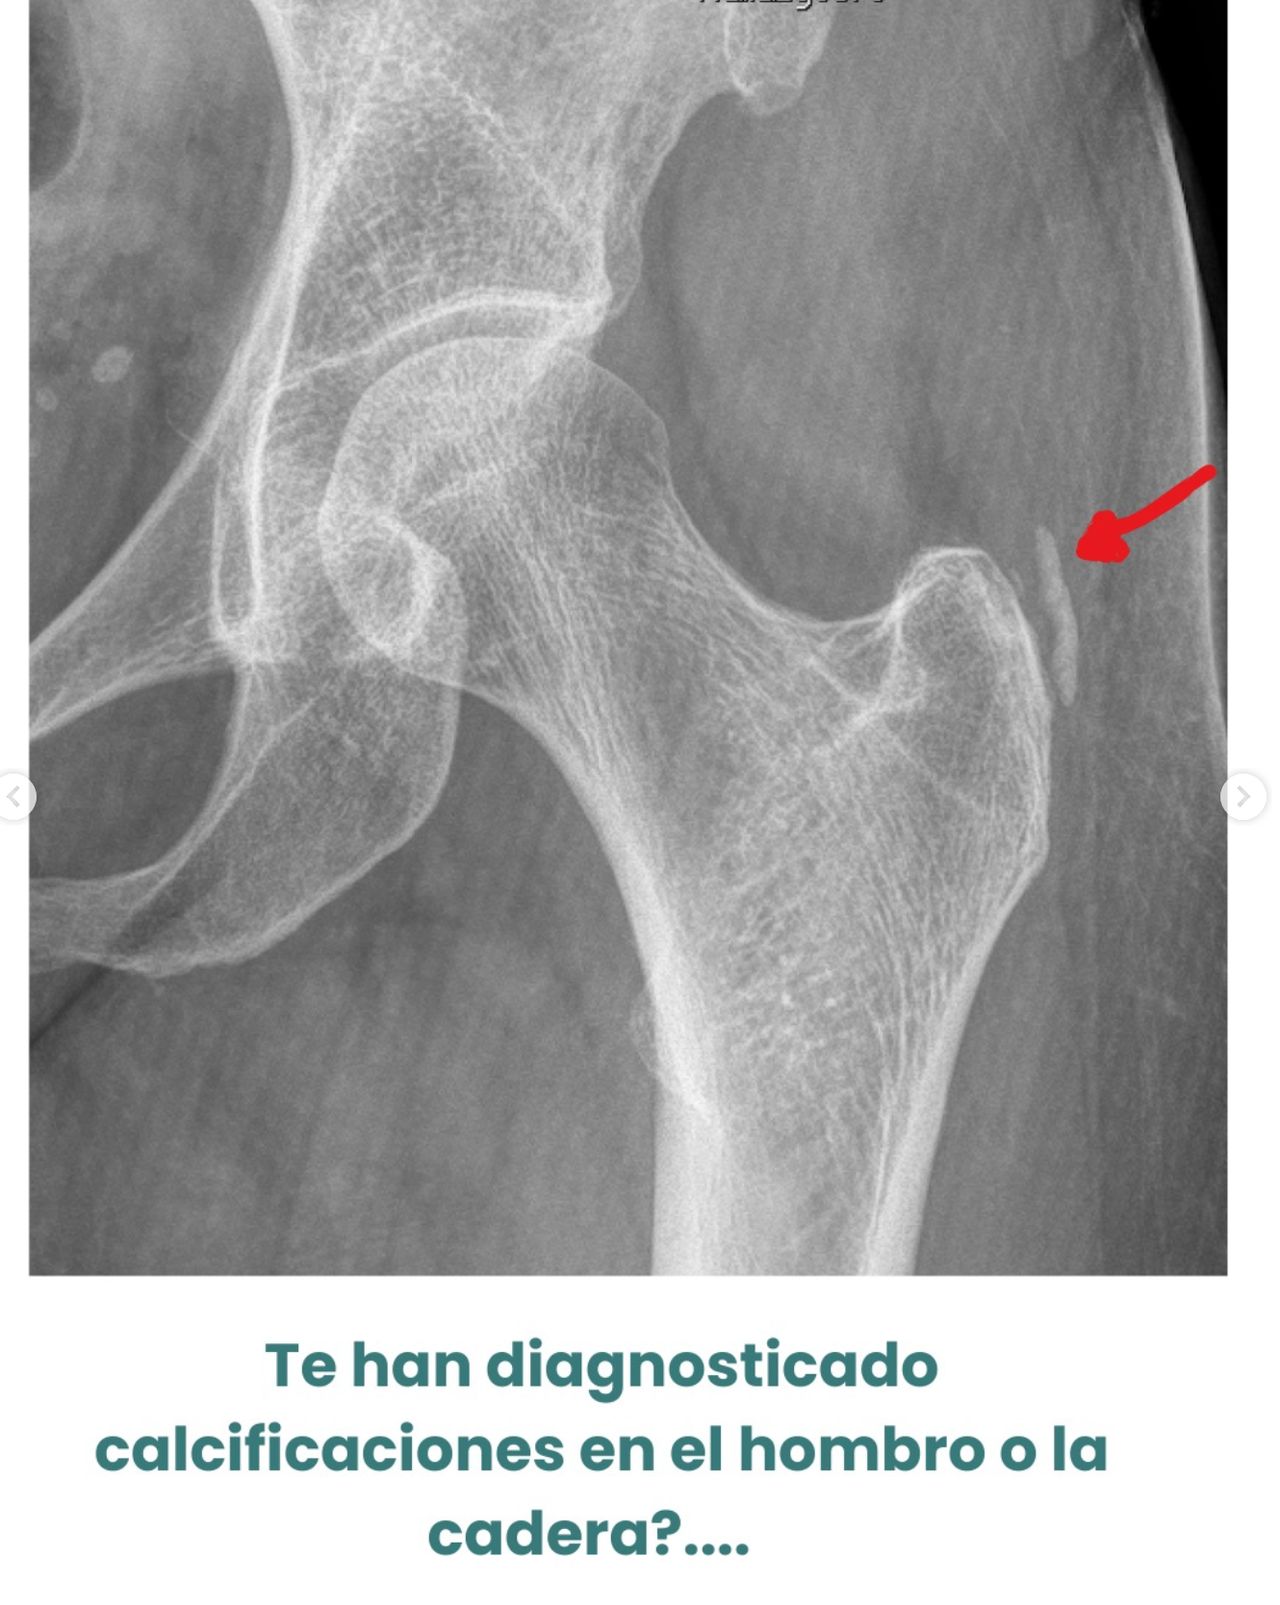

• Calcificaciones del manguito rotador

CADERA / REGIÓN TROCANTÉREA

• Bursitis trocantérea

• Tendinopatía del glúteo medio

• Tendinopatía del glúteo menor

• Síndrome doloroso peritrocantéreo